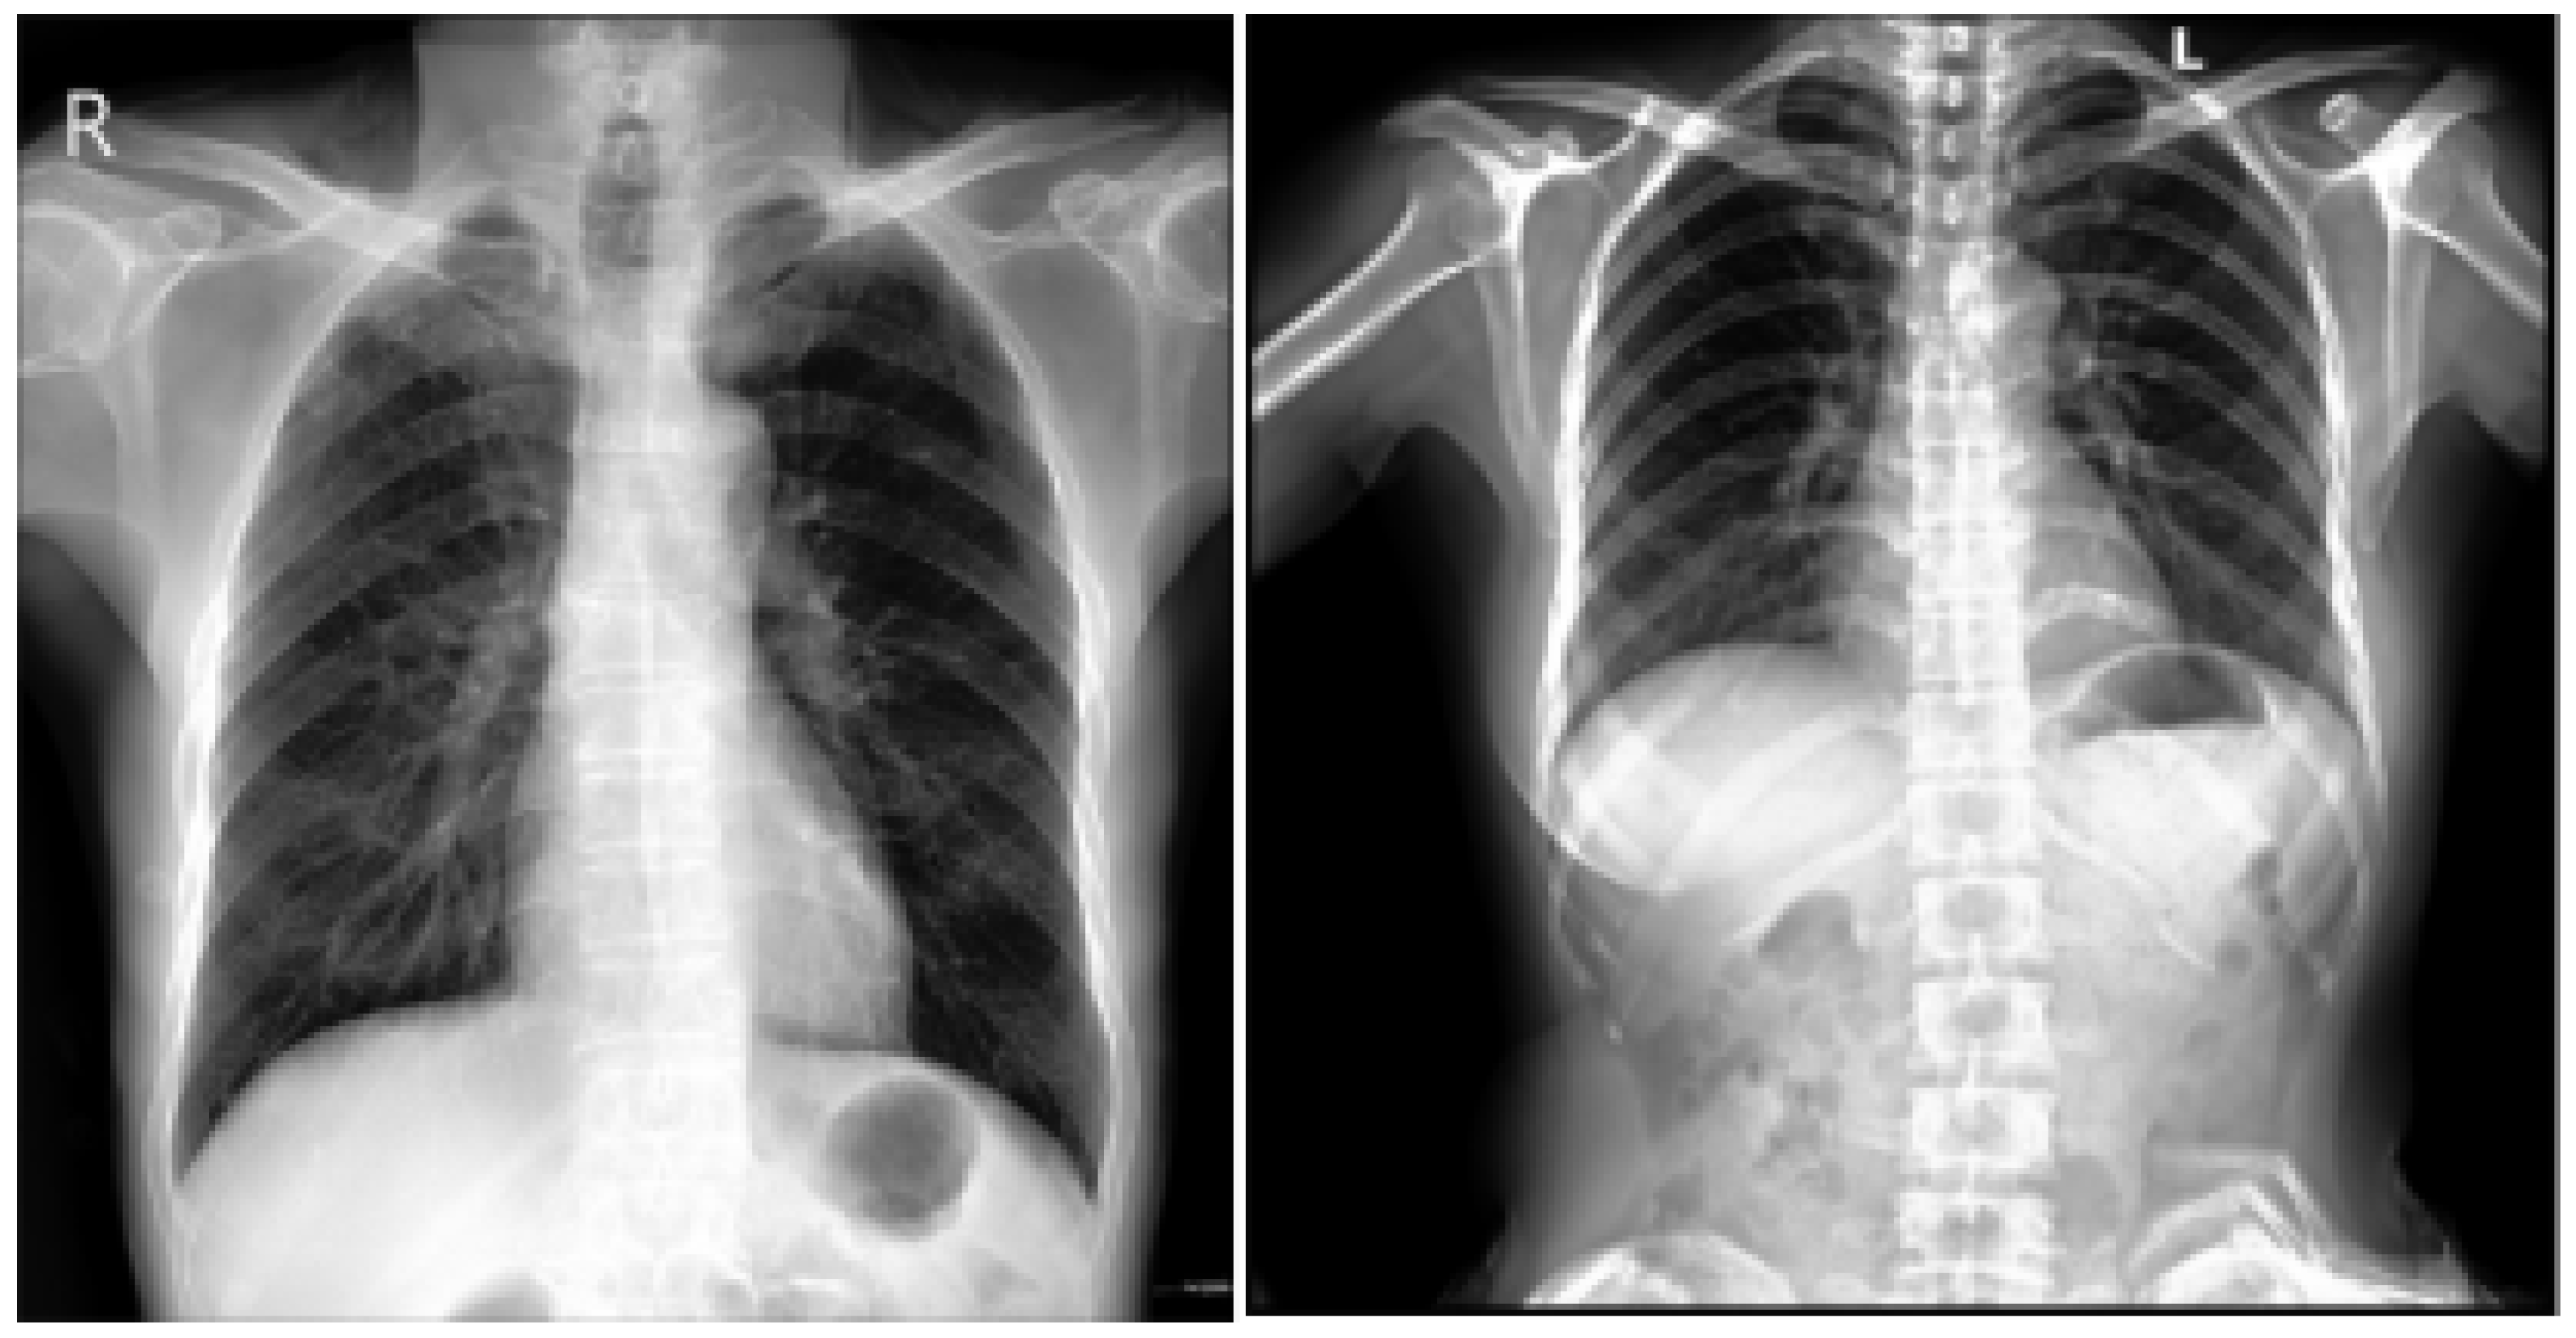

This is an extensive and meticulously curated collection comprising 224,316 chest radiographs obtained from 65,240 patients who underwent radiographic examinations at Stanford Health Care facilities over a substantial timeframe spanning from October 2002 to July 2017 [24,25]. The samples from the CheXpert dataset are shown in Figure 4. These examinations were performed across a diverse range of settings, including inpatient and outpatient centers, ensuring the inclusion of a broad spectrum of clinical scenarios and patient demographics. Each radiograph in this dataset has been labeled for 14 distinct, standard chest radiographic observations, aligning with established clinical guidelines and fostering consistency in labeling across the dataset.

Figure 4.

CheXpert dataset samples [24].